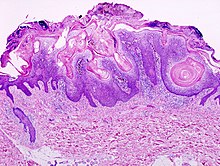

Micrograph of a seborrheic keratosis (H&E stain, scanning magnification)

Visual diagnosis is made by the "stuck on" appearance, horny pearls or cysts embedded in the structure. Darkly pigmented lesions can be challenging to distinguish from nodular melanomas.[9] Furthermore, thin seborrheic keratoses on facial skin can be very difficult to differentiate from lentigo maligna even with dermatoscopy. Clinically, epidermal nevi are similar to seborrheic keratoses in appearance. Epidermal nevi are usually present at or near birth. Condylomas and warts can clinically resemble seborrheic keratoses, and dermatoscopy can be helpful. On the penis and genital skin, condylomas and seborrheic keratoses can be difficult to differentiate, even on biopsy.[citation needed]

A study examining over 4000 biopsied skin lesions identified as seborrheic keratoses showed 3.1% were malignancies. Two-thirds of those were squamous cell carcinoma.[10] To date, the gold standard in the diagnosis of seborrheic keratosis is represented by the histolopathologic analysis of a skin biopsy.[11]